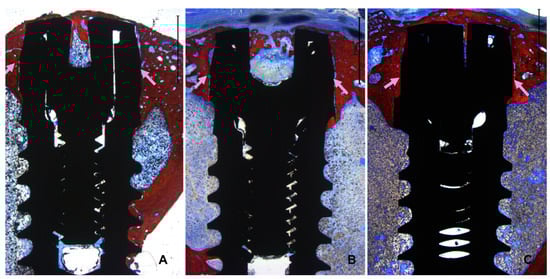

3.2. Descriptive Histological Evaluation

3.3. Histomorphometric Assessments